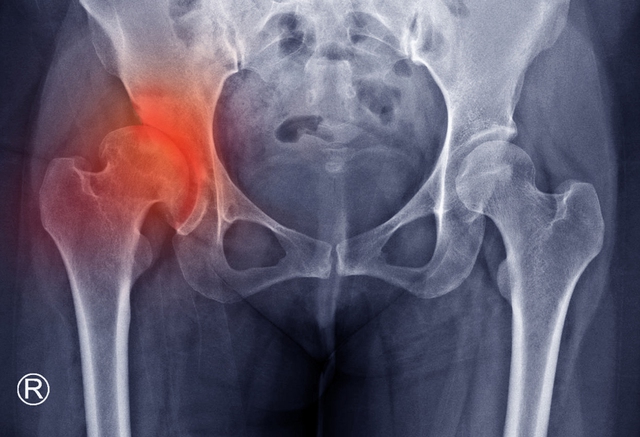

1. Đau hông không do chấn thương và ngày càng nặng hơn

Nếu cơn đau hông của bạn xuất hiện mà không hề có chấn thương hay vận động quá sức nào trước đó, và có xu hướng tăng cường độ theo thời gian thay vì thuyên giảm, đây là một dấu hiệu cảnh báo cần được kiểm tra.

Cơn đau hông này có thể là do ung thư buồng trứng hoặc ung thư tử cung đang phát triển lớn, chèn ép các dây thần kinh và mô xung quanh vùng chậu và hông. Ở nữ giới, khối u buồng trứng thường lan rộng âm thầm, gây ra đau hông khi nó bắt đầu xâm lấn các cấu trúc lân cận. Tương tự, ung thư đại trực tràng ở vị trí sigma hoặc trực tràng cũng có thể gây đau lan xuống vùng hông. Cần lưu ý, đau hông do ung thư thường không thuyên giảm khi nghỉ ngơi hoặc dùng thuốc giảm đau cơ xương khớp thông thường.